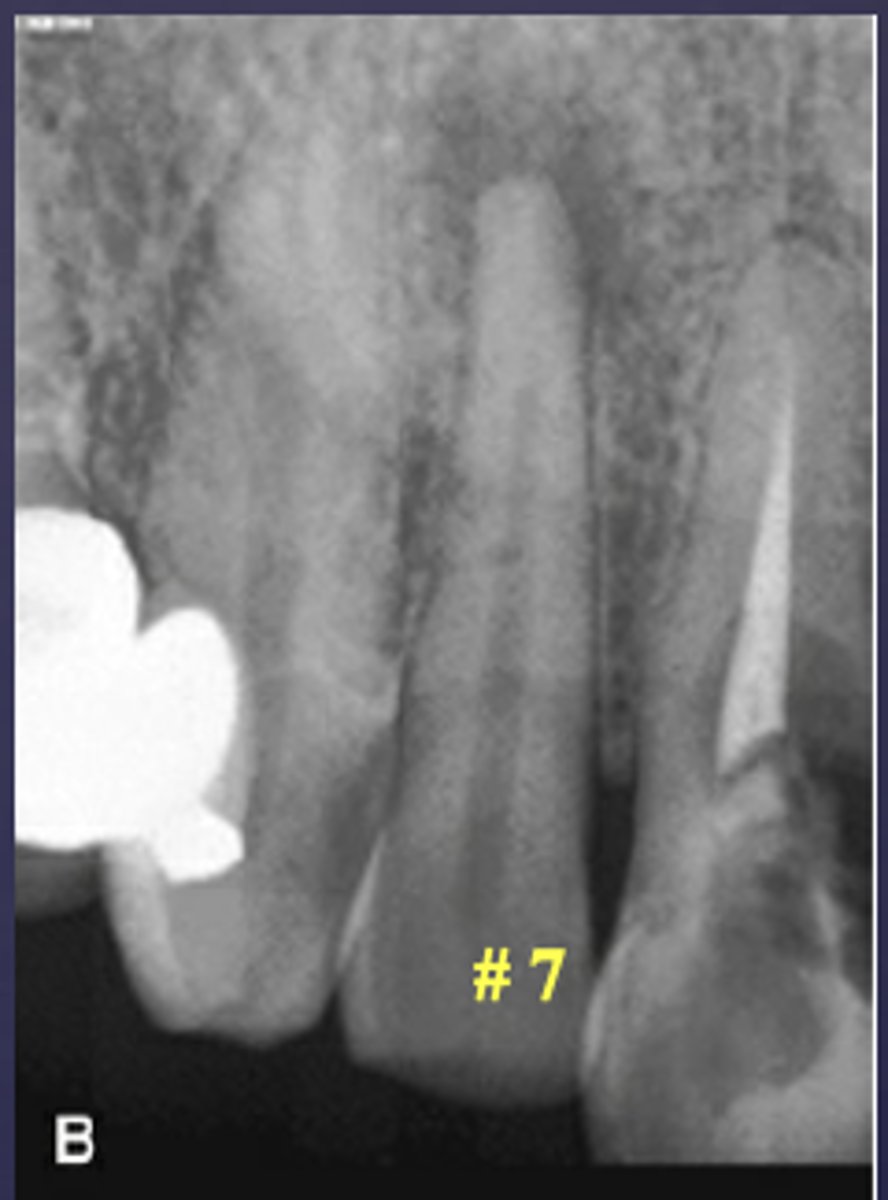

What are two defects that the arrows are pointing to?

- Widened PDL

- Sclerosis

ID the condition:

Carious exposure of pulp

Root fracture